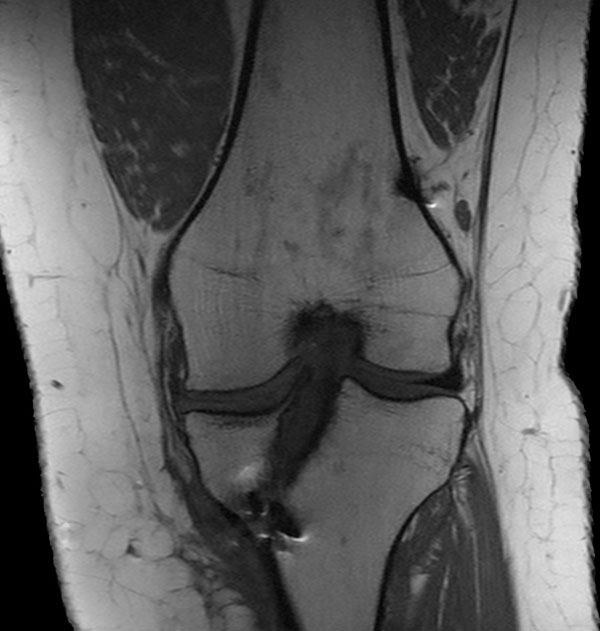

Coronal PDw SPAIR

Coronal STIR aTSE (MARS)

Coronal T1w TSE

Coronal T1w TSE (MARS)